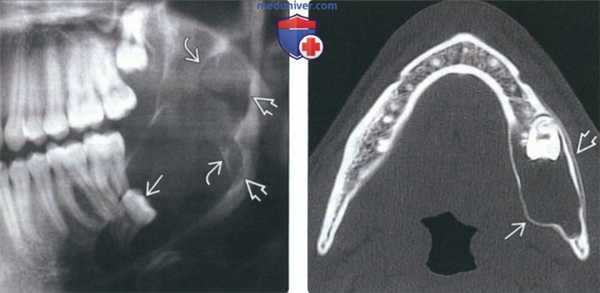

(Слева) На панорамной рентгенограмме определяется четко отграниченное перикорональное просветление, связанное с коронкой импактного третьего моляра нижней челюсти слева. Маленькую зубную кисту невозможно отличить от других перикорональных рентгенонегативных очагов.

(Справа) На панорамной рентгенограмме у этого же пациента четыре года спустя определяется увеличение размеров очага, истончение краевой кортикальной пластинки, гидравлическая экспансия, характерная для зубной кисты. Обратите внимание на смещение корней пораженного третьею моляра сквозь нижний край нижней челюсти. (Слева) На сагиттальной КЛКТ вокруг коронки инвертированного мезиоденса (сверхкомплектного зуба в передних отделах верхней челюсти) определяется большое просветление, отграниченное кортикальной пластинкой. Патологический очаг, прикрепляющийся к ЦЭС, обусловливает легкое вздутие щечной кортикальной пластинки и дна полости носа.

(Справа) На аксиальной КЛКТ у этот же пациента определяется, что патологический очаг доходит до правого клыка и левой верхнечелюстной пазухи. Обратите внимание, что очаг является однокамерным и не содержит кальцинатов. Зуб выглядит как высокоплотное включение в центре очага. (Слева) На аксиальной КЛКТ визуализируются импактные третьи моляры нижней челюсти; справа увеличен зубной фолликул, что сопоставимо с зубной кистой. Сравните с противоположной стороной (норма). Место прикрепления - ЦЭС или область возле него.

(Справа) На аксиальной КТ с КУ в мягкотканном окне визуализируется зубная киста связанная с импактным третьим моляром верхней челюсти справа. Контрастное усиление, позволяющее предположить солидное новообразование, отсутствует. Обратите внимание на край кисты, образованный кортикальной пластинкой, что означает его прорастание в верхнечелюстную пазуху.